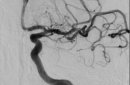

Медикам Орска пришлось столкнуться с непростой задачей — спасти жизнь 16-летнему подростку с инсультом. Благодаря слаженным действиям команды врачей и современному оборудованию, удалось полностью восстановить здоровье юного пациента

Александр Григорьев, заведующий отделением РХМДиЛПервый раз в области инсульт у пациента 16-ти лет. Конечно, все в напряжении были, максимальная мобилизированность. Неврологи, КТ-служба сработали классно и хорошо, все быстро у нас получилось — доставить пациента в операционную. Все происходило быстро, собрано, мобилизовано, все эмоции, все ощущения уже были потом. Как это часто бывает, уже только потом приходит осознание, насколько все серьезно. И, конечно, за судьбой пациента мы очень сильно потом наблюдали, и в тот же день звонили дежурному доктору, и на следующее утро. И потом уже, когда его перевели на второй день в областную детскую больницу, звонили коллегам, узнавали, как дела. Очень сильно радовались, когда узнали, что есть положительная динамика, что он начинает восстанавливаться, да и сейчас даже смотрим и следим за его судьбой, как у него реабилитация проходит, как он восстанавливается. Конечно, для нас это был такой очень эмоциональный опыт. Ну а во время операции, я говорю как есть, ты обычно не сильно эмоционируешь, ты максимально мобилизован и собран, все эмоции потом. Все сложные операции так проходят, по крайней мере у меня. Все осознание — и трясущиеся руки, и красная шея — это уже потом, после операции, когда все закончилось. А во время операции у тебя нет такой опции — включить эмоции.